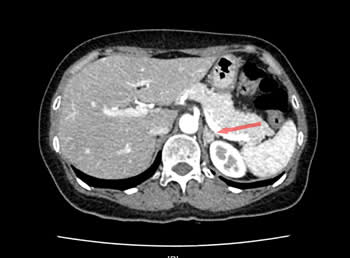

肾上腺CT增强提示左侧肾上腺腺瘤

张女士是一名55岁的高血压患者,血压最高时可达180-190/100-110mmHg,使用3-4种降压药血压勉强控制到140/90mmHg以下。我院心血管专家团队为其进行了醛固酮立卧位试验,提示卧位ARR(血浆醛固酮/血浆肾素)53.1,立位ARR58.20,肾上腺CT增强发现其左侧肾上腺长有腺瘤。在中国高血压联盟副主席、我院心血管内科主任林金秀教授的指导下,彭峰博士和蔡瀚医师借鉴北京阜外医院与上海瑞金医院的先进经验,通过“双侧肾上腺静脉采血”为张女士进行肾上腺腺瘤功能评估。3天后,血液检查结果提示,其左侧选择性指数2.45,证明采血成功(选择性指数>2),左侧肾上腺静脉血醛固酮与外周静脉血醛固酮的比值,较左侧肾上腺静脉血皮质醇与外周静脉血皮质醇的比值未见明显升高,说明张女士左侧肾上腺腺瘤为无功能腺瘤,无需手术治疗,药物控制血压即可。最后,专家团队悉心为张女士的用药进行了调整,在血压的到良好控制后,张女士顺利出院。